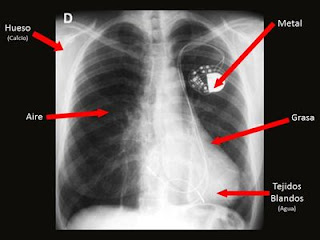

Es una imagen en negativo en donde las áreas correspondientes son estructuras livianas o inexistentes que presentan una máxima señal o densidad óptica (áreas oscuras).Y aquellas secciones de rayos x que atraviesan estructuras densas y muy atenuantes, dan lugar a señales débiles o en una baja densidad óptica (áreas blancas). Por lo cual encontramos en una radiografía 5 densidades básicas que nos permite ver cuales de las estructuras recibió una fuerte dosis de radiación.

DENSIDADES RADIOLÓGICAS